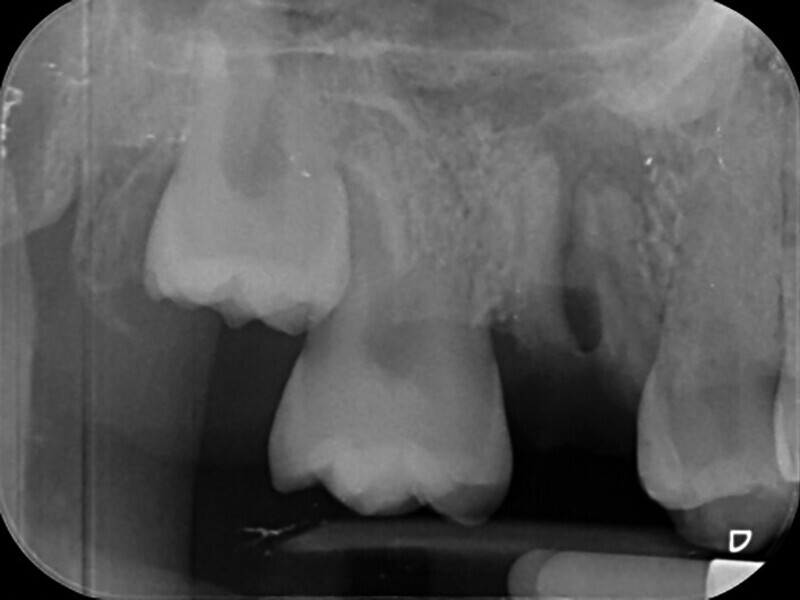

Fig. 2: Pre-op facial view.